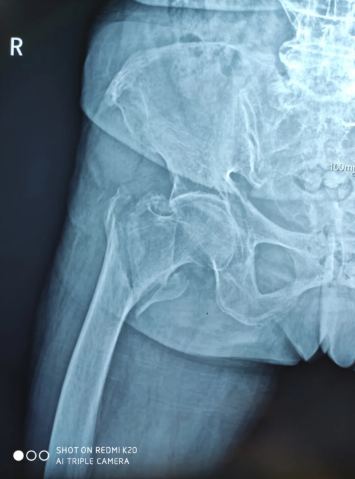

2020年8月15日,90岁高龄的曾老太在家收衣服的时候不慎摔伤在地,当即就感到右髋部剧烈疼痛,且不能行走。家属赶紧拨打医院120急诊电话,随后收治骨科/康复理疗科治疗,经检查确诊:右股骨大小粗隆间粉碎性骨折。

术前X光

然而曾老太患有慢性阻塞性肺疾病、冠心病、心脏扩大、心功能三级、高血压病三级极高危组、脑萎缩、腔隙性脑梗塞等病史,手术治疗非常棘手。